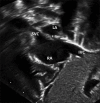

A patent foramen ovale (PFO) is a frequent incidental finding during echocardiography in otherwise healthy children. In most healthy children with a diagnosis of isolated incidental PFO, no further follow-up or intervention is necessary. In some children, PFO is associated with certain clinical syndromes such as cryptogenic stroke, decompression sickness, migraine, and platypnea-orthodeoxia syndrome. This review discusses PFO anatomy, diagnostic imaging, PFO-associated clinical situations, management options, and the role of PFO in certain congenital heart disease. This review also highlights the current deficiency of pediatric data guiding management of these uncommon but important PFO-associated conditions. Future multicenter randomized controlled studies are necessary to guide the management of these unique and challenging PFO-associated conditions.